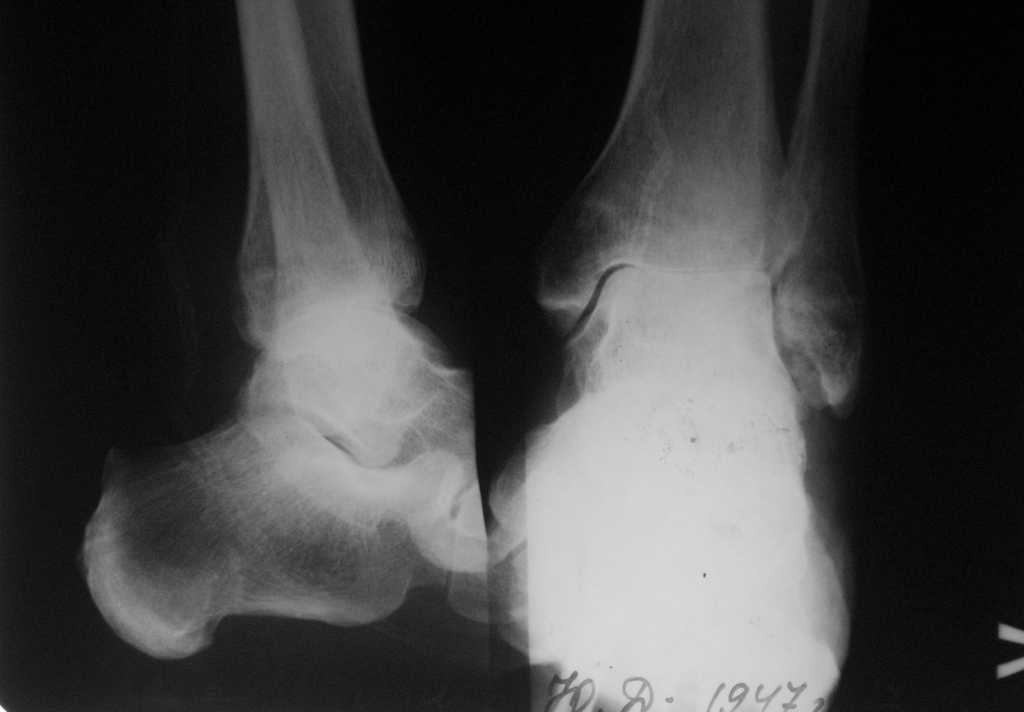

Пациент 57 лет, ранее выполнена пересадка сердца. Травма около 2-х лет назад. В настоящее время- передвигается при помощи костылей, выраженные боли и ограничение движений в голеностопном суставе. На конечность практически не наступает. Активный - рыбалка, охота, дача, дети и внуки.

Коллеги, просьба поучаствовать в обсуждении данного случая особенно тех, кто имел опыт эндопротезирования голеносторного сустава. Сам пациент настроен на протез, мы предлагаем артродез системой T2AAN Stryker.